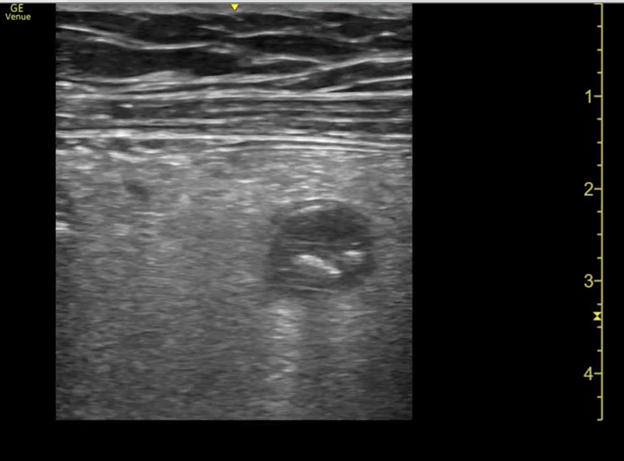

A 14-year-old female with a past medical history of anxiety and bipolar disorder presented to the emergency department with constant, sharp, non-radiating right lower quadrant abdominal pain. The pain began suddenly two nights ago and worsened with movement. She denied nausea, vomiting, diarrhea, fevers, or chills. On physical exam, her abdomen was tender to palpation in RLQ and RUQ with rebound and guarding. Labs demonstrated a leukocytosis of 12.9k with no other remarkable abnormalities. Given the broad differential of appendicitis vs ovarian torsion vs gallbladder disease, bedside ultrasound was performed. A non-compressible dilated appendix 7.3mm in diameter with an appendicolith present. (Image 1) Comprehensive radiology ultrasound of the abdomen demonstrated a non-peristalsing 6.5 x 1.1 x 1.6 cm tubular structure in the right lower quadrant concerning probable appendicitis. General surgery was consulted, and the patient underwent a laparoscopic appendectomy the same day. She underwent the procedure without complication and was discharged the following day.

Image 1. Image from case showing a dilated appendix suggestive of acute appendicitis with appendicolith and target sign present.

When appendicitis is present, the appendix will measure greater than 6 mm from outer wall to outer wall, with a wall thickness greater than 3 mm and lack compressibility. (Images 1, 8, and 9) (Remember, you may want to do these measurements after you have obtained your images, given your patient a high five and a sticker, and stepped aside to perform measurements on the machine.) An inflamed appendix can demonstrate a “ring of fire” with enhanced color flow. Secondary findings you may see include: an appendicolith, (Image 1), periappendiceal free fluid (Image 10), a target sign (Image 1), enlarged mesenteric lymph nodes, thickening and hyperechogenicity of the overlying peritoneum (Image 8), dilated and hypoactive small bowel, and thickening of the apical cecal pole.